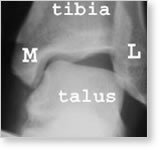

Normal Ankle

Front of the ankle.

M= medial malleolus, L=lateral malleolus (fibula). The outside of the heel is pushed inwards to stress the joint. In the normal ankle, no tilting of the ankle should occur at all. Note the tilting of the talus in the ankle.